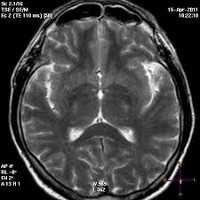

КТ или МРТ: определяются симметричные множественные очаговые изменения и умеренно выраженные признаки «масс-эффекта», иногда признаки компрессии боковых желудочков, фокальный или диффузный отек головного мозга, микрогеморрагии.

- Томография.МРТ головного мозга - наиболее информативный метод в диагностике морфологических изменений мозговых тканей. Позволяет выявить диффузные дегенеративные изменения, очаги перенесённых лакунарных инфарктов у пациентов с II - III стадией ГЭ, исключить прочую органическую патологию мозга.

При наличии пароксизмальной активности показано проведение электроэнцефалографии, консультация эпилептолога. Выявление почечной дисфункции по результатам лабораторных анализов является поводом для включения в перечень необходимых обследований УЗИ почек и консультации нефролога. Дифференцируется энцефалопатия гипертонического генеза от опухоли головного мозга, энцефалита, медленных инфекций ЦНС, болезни Паркинсона, демиелинизирующих заболеваний, болезни Крейтцфельдта-Якоба, Альцгеймера. На сосудистый характер поражения указывают данные цереброваскулярных исследований, обнаружение на МРТ следов лакунарных инфарктов.

При КТ и МРТ головы определяются симметричные множественные очаговые изменения или сливающиеся гиподенситивные поля, соответствующие субкортикальному белому веществу затылочной или теменно-затылочной локализации. Много реже аналогичные изменения выявляются в мозжечке, стволе мозга, других областях больших полушарий.

Можно обнаружить умеренно выраженные признаки "масс-эффекта", иногда - компрессию боковых желудочков. Приоритетным методом нейровизуализации является МРТ головы в Т2 режиме.